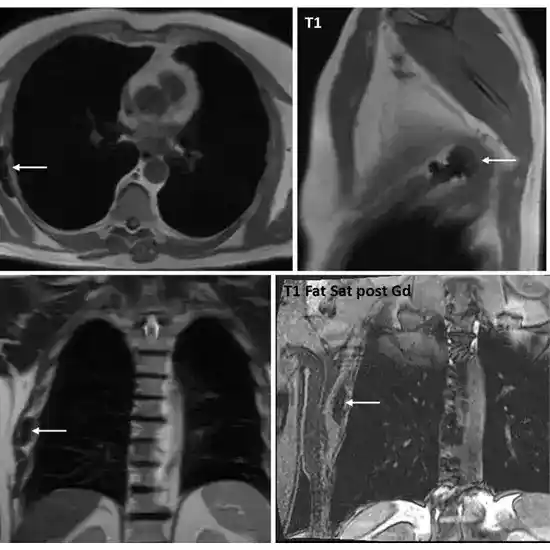

Product Name: Chest mri hotsellChest MRI Protocols and Planning Indications for MRI Chest Scan hotsell, MRI Chest Process And Diagnosis hotsell, What Is Chest MRI StoryMD hotsell, MRI of the lung 2 3 Why when how Insights into Imaging Full Text hotsell, Chest MRI Magnetic Resonance Imaging hotsell, What Should I Expect From A Chest MRI South Jersey Radiology hotsell, Chest MRI Protocols and Planning Indications for MRI Chest Scan hotsell, MRI Chest Cost Purpose Procedure Results 2025 hotsell, The role of MRI in comparison between benign and malignant chest wall masses in correlation with pathology Egyptian Journal of Radiology and Nuclear Medicine Full Text hotsell, Ten years of chest MRI for patients with cystic fibrosis Die Radiologie hotsell, Chest MRI Information Mount Sinai New York hotsell, MRI Chest Test Price in Delhi Ganesh Diagnostic hotsell, Cardiac MRI Stress Cardiac Perfusion MRI or Chest MRI hotsell, Practical protocol for lung magnetic resonance imaging and common clinical indications Pediatric Radiology hotsell, Chest MRI Purpose Procedure and Risks hotsell, MRI chest. MRI of the chest on axial sections reveal a large well. Download Scientific Diagram hotsell, MRI Chest near me in Orlando FL Imaging center Orlando hotsell, Chest MRI Information Mount Sinai New York hotsell, Chest MRI scan showing a solid hypervascularized middle mediastinal. Download Scientific Diagram hotsell, MRI Finds Lung Abnormalities in Non hospitalized Long COVID Patients Imaging Technology News hotsell, Anterior chest wall inflammation by whole body magnetic resonance imaging in patients with spondyloarthritis lack of association between clinical and imaging findings in a cross sectional study Arthri... hotsell, Is it Cyst or Neoplasm The Role of Thorax Magnetic Resonance Imaging Archivos de Bronconeumologia hotsell, 1 300 Chest Mri Stock Photos Pictures Royalty Free Images iStock Mri scan Lung mri Ct scan hotsell, Pulmonary Mediastinal Vascular and Chest Wall MRI Radiology Key hotsell, Chest MRI of patients with COVID 19 a retrospective case study medRxiv hotsell, Normal Magnetic Resonance Imaging of the Thorax Magnetic Resonance Imaging Clinics hotsell, The role of MRI in comparison between benign and malignant chest wall masses in correlation with pathology Egyptian Journal of Radiology and Nuclear Medicine Full Text hotsell, The use of chest magnetic resonance imaging in interstitial lung disease a systematic review European Respiratory Society hotsell, Chest Anatomy MRI Chest Thorax Axial Anatomy Free Cross Sectional Heart Anatomy hotsell, Woman s chest MRI scans hotsell, Contrast Mri Chest in Chandigarh at best price 8699572364 hotsell, Check the chest review of chest findings on abdominal MRI ScienceDirect hotsell, Chest MRI Image Photo Free Trial Bigstock hotsell, Anterior chest wall inflammation by whole body magnetic resonance imaging in patients with spondyloarthritis lack of association between clinical and imaging findings in a cross sectional study Arthri... hotsell, 12 Conditions a Chest CT Scan or MRI Scan Can Help Diagnose Charlotte Radiology hotsell.